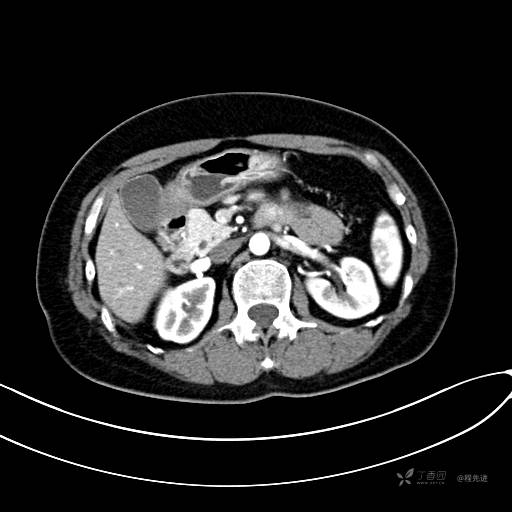

CT平扫